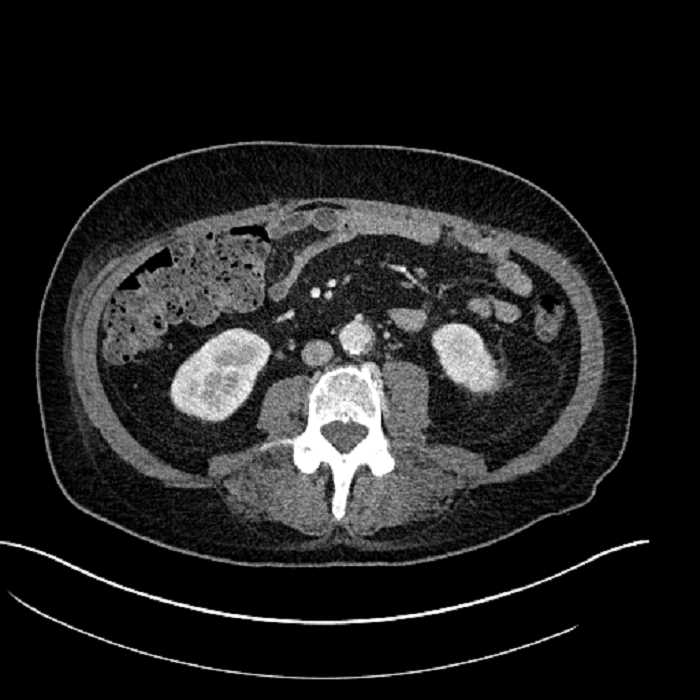

• Large fluid density structure in hepatic segments 7 and 8 measuring 10 x 7 x 7 cm with internal septation and circumferential ill-defined low density compatible with edema

• Peripherally enhancing subcapsular collections along the anterior margin of the left hepatic lobe measuring 3 x 1 cm and 2 x 1 cm

• Clearly marginated fluid density structure in segment 7 and several other scattered tiny hypodensities, which likely represent cysts

Acute sigmoid diverticulitis complicated by a small contained perforation and a large abscess in the right hepatic lobe. Additional small subcapsular abscesses along the anterior margin of the left hepatic lobe.

• The classic CT imaging appearance is a double target sign with internal low density surrounded by an internal enhancing rim (capsule) and a low density external rim (edema)

Hepatic abscess showing the double target sign with low density internally surrounded by a thin inner enhancing rim (red arrow) and ill-defined outer low density rim (yellow arrow). Blue arrow indicates an internal septation. Red arrows: additional smaller subcapsular abscesses. Red arrow: focal contained perforation associated with diverticulitis.